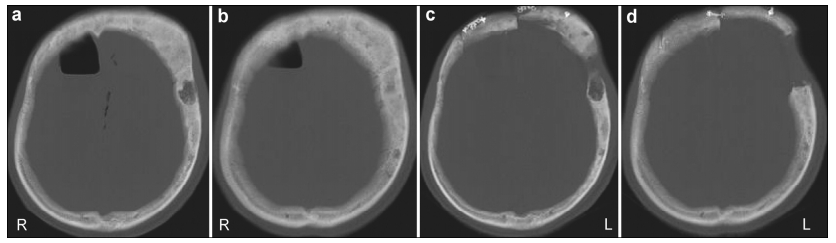

2 Case study 2.1 History and examinationA 30-year-old man presented with a 20-day history of clear discharge from his right nostril. He suffered from a mild head trauma 40 days before counseling at our institution. Laboratory tests of the discharge showed a glucose level of 3.73 mmol/L. This high glucose level suggested that the discharge was CSF. Physical examination showed that the patient’s left eye and left frontal part were more prominent than the equivalent right side. According to the patient’s recall, these symptoms first appeared at the age of twenty and had changed slowly since then. Computed tomography (CT) cisternogram located the site of the defect in the posterior wall of the right frontal sinus and demonstrated the evident expansion of multiple skull bones (Figure 1). Lumbar puncture was done and intracranial pressure was 150 mm H2O.

| Figure 1 (a, b) A computed tomography (CT) scan demonstrating the expansion of multiple skull bones. The involved bones present with various appearances of mixed radio-dense/radio-lucent lesions, which can be described as “ground-glass”, “lytic”, and “cystic”. Left: Axial CT cisternography demonstrates a fistula at the posterior wall of the right frontal sinus (white arrow). The density of both frontal involved bones is slightly lower than for other skull bones. Right: A coronal CT scan demonstrates pneumocephalus in the right frontal lobe (black arrow). |

The first was pathological changes in the skull bone. FD is characterized by the excessive formation of fibrous tissue in the bone marrow and the destruction of normal bone in conjunction with abnormal bone formation and increased osteoclast activity[11]. Normal bone tissue is replaced by the gradual abnormal pro-liferation of fibrous tissue[9]. These pathological changes weaken the structural integrity of the involved bones[12]. Under slight stress, these bones tend to deform and might even fracture[13]. As the limbs, especially both lower limbs, usually bear most of the mechanical stress during daily life, pathologic fractures often occur in these bones with FD. Without significant stress, skull bones with FD rarely fracture. However, when a CFD patient suffers from head trauma, these skull bones might fracture more easily than normal bones. In our patient, CFD was involved in multiple skull bones, including the right frontal bone. A CT scan indicated a low density of the involved right frontal bone (Figure 1), and enhanced MRI showed evident enhan-cement of the right frontal sinus wall (Figure 4). This suggested that the bone in right frontal sinus wall contained numerous small vessels and fibrous elements[3], which would decrease the strength of the bone. These pathological changes increased the risk of fractures after head trauma. As the enhanced MRI was performed after surgery, the enhancement of right frontal sinus posterior wall might also be caused by a healing reaction. However, because the anterior wall of right frontal sinus and surrounding involved bones were also enhanced, it was reasonable to presume that the enhanced effect was mainly caused by pathological changes due to FD.

The second factor was increased intracranial pressure associated with CFD that might contribute to CSF rhinorrhea. In this case, a CT scan demonstrated significant thickening and expansion of multiple skull bones, decreasing the cranial cavity (Figure 1). However, before the head trauma, this patient did not have symptoms associated with increased intracranial pressure, including headache, nausea and vomiting. This suggested that before the trauma, the patient’s intracranial pressure was well compensated. However, as the cranial cavity was decreased after trauma, this compensation for a higher intracranial pressure was constrained. During the period of trauma, both the swelling of the brain and pneumocephalus might have contributed to the increased intracranial pressure. Without good compensation ability, the patient’s intracranial pressure increased. Although the intrac-ranial pressure measured by lumber puncture before the fistula repair surgery was normal, this might have been associated with an alleviation of the swelling brain after a forty-day recovery and the discharge of CSF through the fistula. To increase the cranial cavity, we contoured the excised bone to be thinner before it was placed back during the fistula repair surgery. This treatment effect was satisfactory (Figure 3).

In this case, CSF rhinorrhea began about twenty days after the head trauma. Initially, the fistula might be temporarily blocked by tissues such as the brain, granulation tissue, and sinus mucosa[14]. Sometimes, CSF leakage can occur more than 3 months after head trauma, termed delayed onset of CSF rhinorrhea[15]. Spontaneous CSF rhinorrhea has also been reported in various anterior cranial base pathologies, such as osteoma, pituitary adenoma, primary empty sella, and chordoma[16-19]. Spontaneous CSF rhinorrhea may be caused by pathological invasion of the cranial base or intracranial hypertension[20, 21]. Although it was reported that CFD may have a tendency for spontaneous CSF leakage[22], there have been no related case reports published to the best of our knowledge. Our case report may provide support to the idea that CFD may have a tendency for spontaneous CSF leakage. However, in some situations, CFD may decrease the risk of CSF rhinorrhea. For example, if the cavity of the paranasal sinus is filled with expanded bone tissue as in the left frontal sinus of our patient (Figure 1), CSF cannot drain out through the paranasal sinus. Furthermore, if the wall of the paranasal sinus contains more osseous elements, the bone strength is stronger and less likely to fracture. Therefore, whether CFD increases the risk of CSF rhinorrhea in different situations needs to be evaluated.

The surgical treatment of CFD aims to correct the facial deformity in most cases and restore the obliterated foramina, when it the cause of problems. However, this can result in recurrence in 15%-20% of all cases, especially during the growth period[7, 23]. The most devastating consequence of CFD is the loss of vision due to optic nerve compression (ONC). There has been significant controversy regarding the manage-ment of FD of the sphenoid bones that encase the optic nerve, particularly in patients whose vision is normal. A meta-analysis[24] showed that most patients with CFD remain asymptomatic during long-term follow-up, and therefore expectant management is recommended in asymptomatic patients even in the presence of radiological evidence of ONC. Lee et al.[5]recommended that FD in the skull base around vital structures, including the optic nerve, should be managed according to the clinical examination and regular diagnostic imaging and observation is appro-priate in asymptomatic patients. When visual change or vision loss occurs due to ONC, decompression surgery can be performed. In this case, the patient’s age was over 30 years and a CT scan of the involved skull bones showed a mixed appearance (Figure 1). This indicated that the involved bones had entered a stable period. However, nineteen months later, sight in the patient’s left eye had decreased. A CT scan showed that compression of the left optic nerve was more severe than at nineteen months previously (Figure 5). MAS was suspected. Unfortunately, the patient refused to undergo the proposed decompression surgery and laboratory tests of serum hormones.